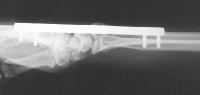

Clinical Example: Distraction plate fixation of distal radius fracture

Click on each image for a larger picture